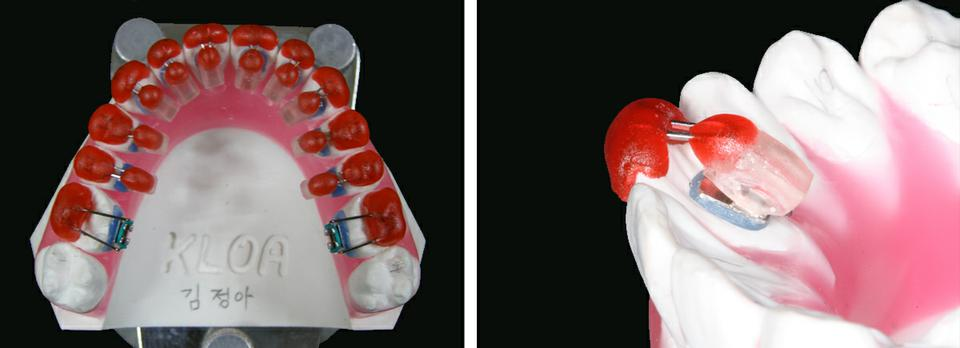

• 2. Bracket customization

Setup model에서, 안보이니 설측 브라켓은 각 치아에 맞는 처방을 갖도록 부착됩니다. 특별한 브라켓 위치기구를 이용해, 브라켓들은 ideal setup에 광중합 레진으로 부착됩니다.

각 환자에 맞는 처방에 따라 각 브라켓에 torque, in-out, angulation이 맞춤 제작됩니다. 맞춤 제작된 torque, in-out, angulation은 각 브라켓 베이스의 레진에 내장됩니다.

• 4. Individual transfer tray

브라켓을 정밀하고 효율적으로 환자의 치아에 전달하기 위해 셋업 모형에서 바로 individual transfer tray를 제작합니다. Group transfer tray와 비교해, individual transfer tray는 향상된 정확성, 모든 경우에 적용할 수 있는 능력, 개별 브라켓의 이상적 위치 재현성을 제공합니다.